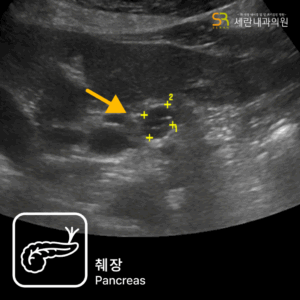

가스 차는 증상과 경미한 혈변으로 발견된 직장암 사례설사와 혈변, 항문 통증으로 내원했다가 직장암을 진단받은 40대 남성 사례심한 변비로 내원하여 상행결장암을 진단받은 80대 남성 사례속쓰림으로 내원했다가 복부초음파로 조기 담낭암을 발견한 사례명치 통증과 소화불량으로 내원했다가 췌장암 3기가 진단된 사례무증상 검진 중 갑상선초음파로 발견된 조기 갑상선 유두암 사례유방 통증으로 내원했다가 유방초음파로 조기 진단된 침윤성 유방암 사례명치 통증으로 내원했다가 진행성 위암을 발견한 60대 여성 사례속쓰림으로 내원했다가 signet ring cell type 위암을 조기 발견한 60대 여성 사례소화불량으로 내원했다가 작은 조기 위선암을 발견한 50대 여성 사례변비로 내원했다가 침윤성 궤양 형태의 위암을 발견한 70대 여성 사례소화불량으로 내원했다가 진행성 위암을 발견한 60대 여성 사례경미한 속쓰림으로 방문했다가 조기 위선암을 발견한 60대 여성 사례가스 차는 증상과 경미한 혈변으로 발견된 직장암 사례설사와 혈변, 항문 통증으로 내원했다가 직장암을 진단받은 40대 남성 사례심한 변비로 내원하여 상행결장암을 진단받은 80대 남성 사례속쓰림으로 내원했다가 복부초음파로 조기 담낭암을 발견한 사례명치 통증과 소화불량으로 내원했다가 췌장암 3기가 진단된 사례무증상 검진 중 갑상선초음파로 발견된 조기 갑상선 유두암 사례유방 통증으로 내원했다가 유방초음파로 조기 진단된 침윤성 유방암 사례명치 통증으로 내원했다가 진행성 위암을 발견한 60대 여성 사례속쓰림으로 내원했다가 signet ring cell type 위암을 조기 발견한 60대 여성 사례소화불량으로 내원했다가 작은 조기 위선암을 발견한 50대 여성 사례변비로 내원했다가 침윤성 궤양 형태의 위암을 발견한 70대 여성 사례소화불량으로 내원했다가 진행성 위암을 발견한 60대 여성 사례경미한 속쓰림으로 방문했다가 조기 위선암을 발견한 60대 여성 사례